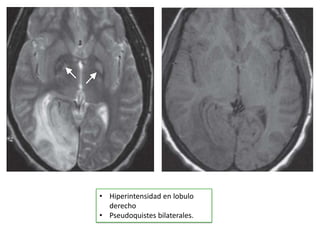

• Hiperintensidad en lobulo

derecho

• Pseudoquistes bilaterales.

• Hiperintensidad enlobulo derecho • Pseudoquistes bilaterales.